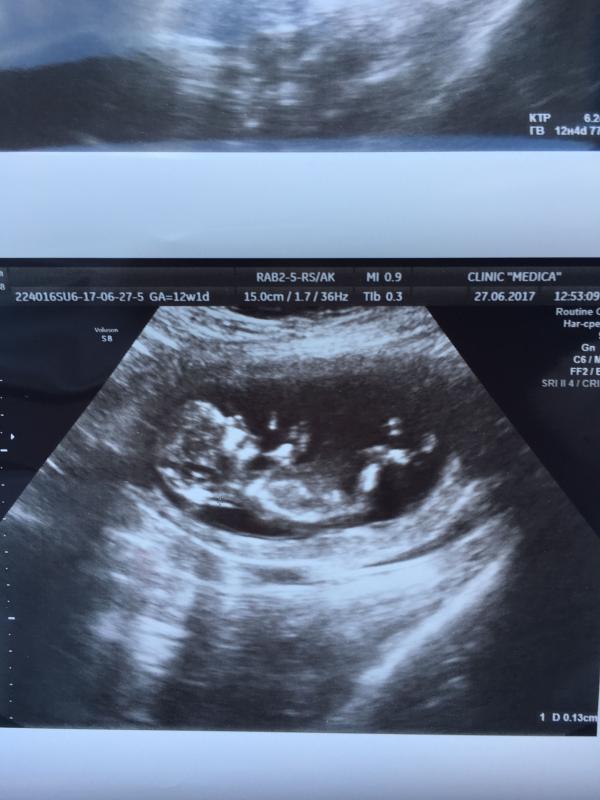

Ну вот и первый скрининг позади, по УЗИ все отлично 👍, растёт наш малыш🐣 завтра ещё кровь сдать и пока все) чувствую себя замечательно, если б не эта фотка и чувство что кто то внутри, то беременной меня сложно назвать)

@askala, в медику ходила, на будущее вам рекламка 😊там конечно УЗИ делают лучше чем в Жк у нас

@elmofeo, ой лялька 🙏🏻🙃нам в 12,4 предположили мальчика ))) так как развивается на неделю вперед сказали 80% ))) два раза уже подтвердили ))) ждём сыночка )))